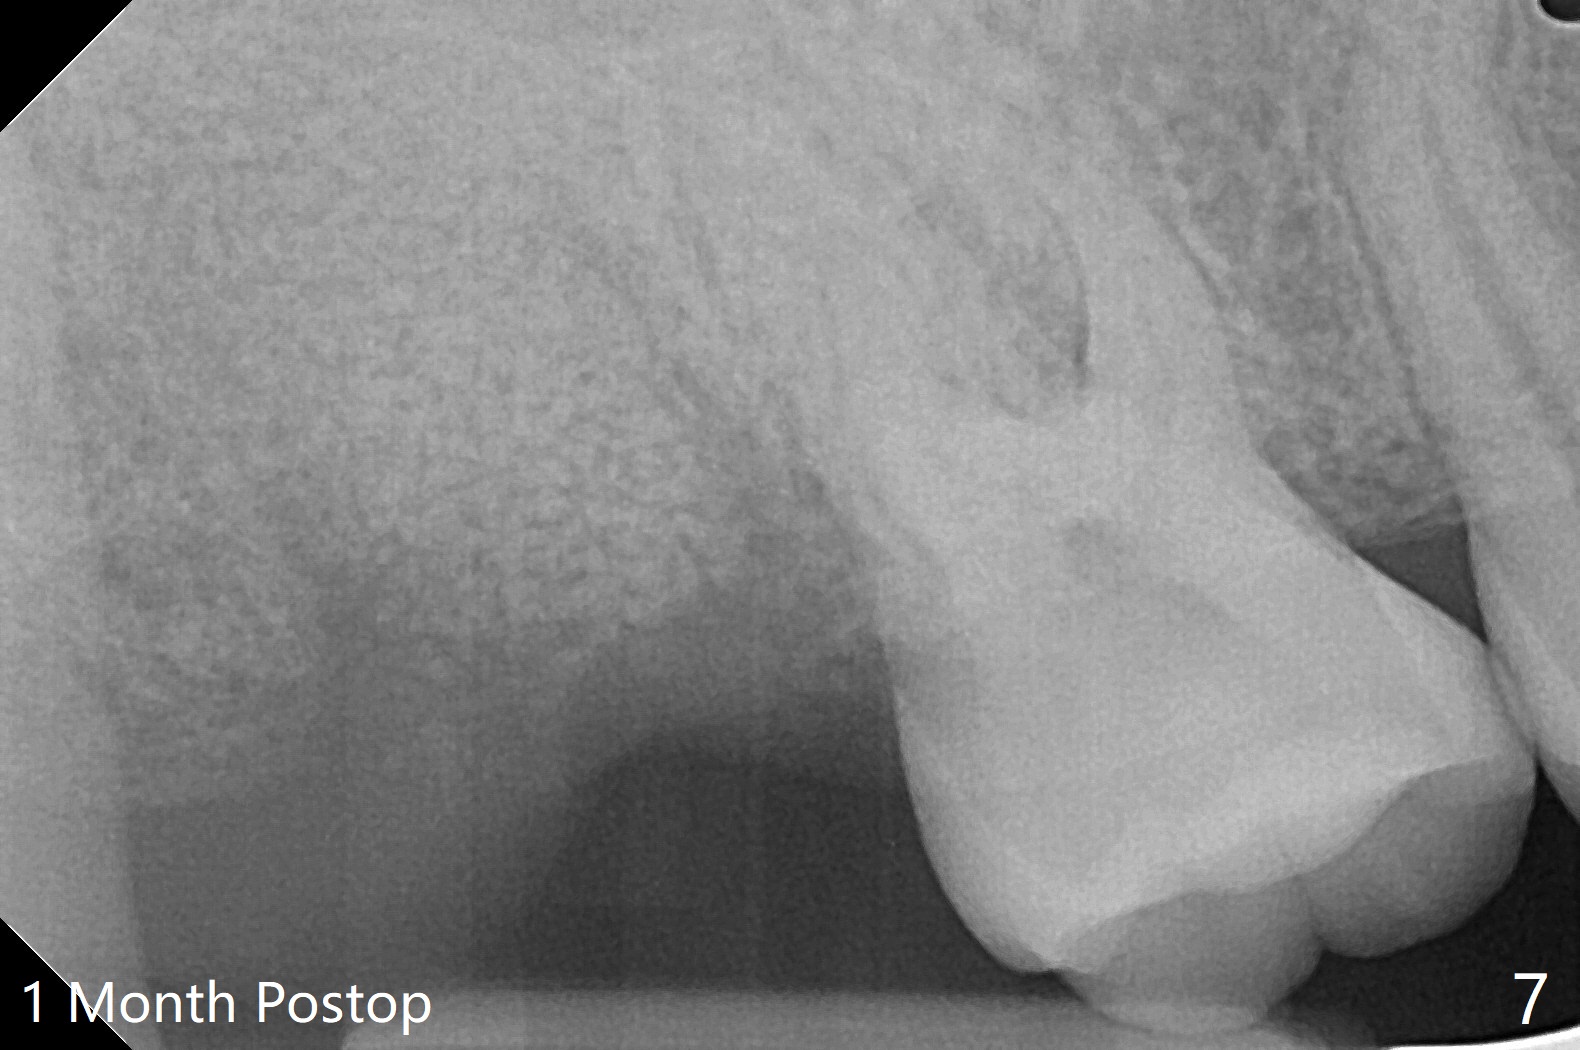

31岁女去年10月份就诊,右上7隐裂(图一),提出根管治疗,牙冠或者拔除,植牙。她犹豫不决,因为今年6月份回国。昨天因腭侧脓肿深度牙周袋复诊,最后同意拔除,植骨。使用GEM21S(血小板因子,没有时间抽血)与皮质骨粉(加一些人工骨)调袢(图二:*),覆盖不可吸收膜(Cytoplast,一张~$50,剪半可用于两个磨牙牙槽窝,买一盒十张,赠送两个PTFE缝线(最近促销);图三)。PTFE,Cytoplast以及Plumber tape据说来自同一个材料,至少前两者最好同时用。但是这个病例,助手打开PGA缝线后,我们才知道Cytoplast刚刚到,它的好处在于暴露于口腔,下面骨粉几乎不会感染。五周后撤除 ,下面骨粉一般愈合正常,接近百发百中。想不到垂直距离特别短,没有空间放置空间保持器,后者有利于牙周敷料固定,下颌第二磨牙牙尖咬到保持器攀(loop),尽管保持器已经放置第一磨牙颈部。无可奈何,在缝线周围涂牙周胶水(图三:蓝紫色)。术后两周膜已经脱落(图四),但是下面骨粉好像没有丢失太多(图五)。两周后伤口愈合(图六)。骨粉失去不多(图七)。